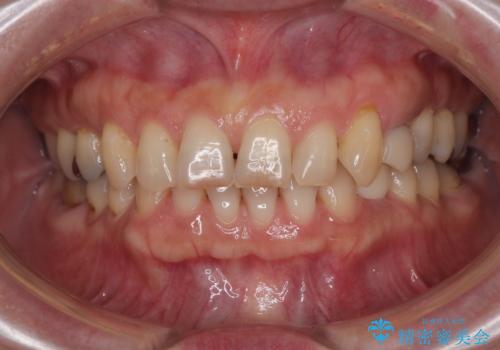

そこで今回は、抜歯と同時にインプラントを埋入する「抜歯即時インプラント治療」をご提案。

外科処置の回数を抑え、治療期間を短縮できる点が大きなメリットです。

治療は計画通りに進み、約3か月で最終補綴まで完了。

見た目だけでなく、しっかり噛める機能も回復し、患者様にも大変ご満足いただけました。